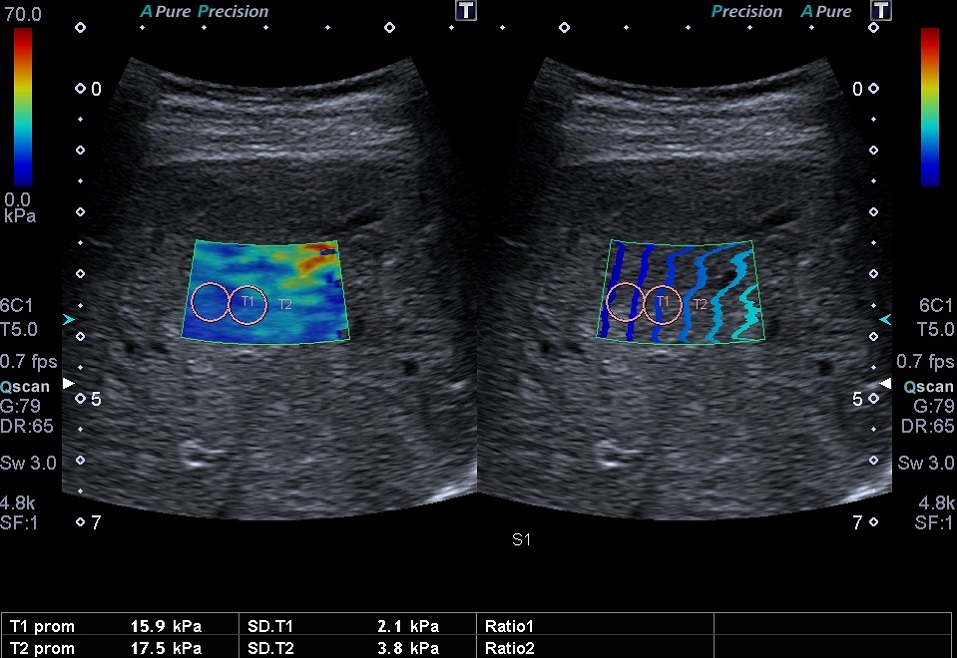

En la última revisión se realiza una ecografía abdominal, donde se observa un hígado de tamaño conservado y ecogenicidad heterogénea con áreas parcheadas hiperecogénicas (Fig. 1), ausencia de lesiones focales, y flujos vasculares sin alteraciones. En la elastografía se registraron valores aumentados, de hasta 20 kPa (Fig. 2). Se inició un programa de seguimiento periódico por parte de la sección de gastroenterología, con realización de ecografías-elastografías seriadas, cada seis meses.

Elevación leve de los valores de medición en estadios iniciales (congestión venosa) Elevación más marcada (>15 kilopascales) en cuadros evolucionados, por fibrosis8-10 |